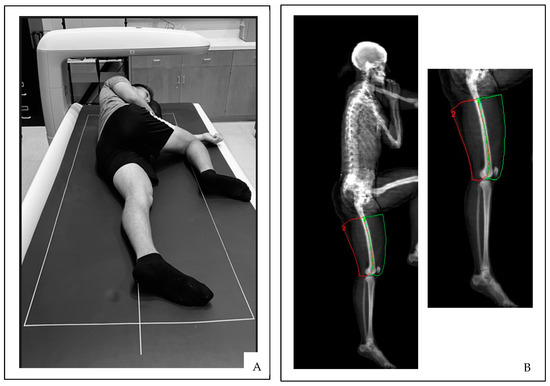

The total body DXA scans were performed by a single trained investigator. All DXA scans were analyzed using GE Lunar software version 14.10. The first total body DXA scan was performed with the subjects lying in the standard anterior/posterior scanning position. This total body DXA scan was analyzed by the DXA scanning technologist (Investigator 1) to provide demographic information, including the total body absolute fat-free and MFL masses and the absolute and relative fat mass. Immediately following the first scan, two additional total body DXA scans were performed with the subjects lying on their left and right sides while the leg of interest was extended and the contralateral leg bent to avoid interference from the analysis field of view (Figure 1A).

Unique ROI were created for soft tissue analyses of mineral-free lean masses (MFL; g) using custom analysis software with manual tracing of the quadriceps (QUADS) and hamstrings (HAMS) of the right and left thighs. Anatomical landmarks were identified as the center of the femur (identified as the middle of the femur shaft) and soft tissue borders for the medial and lateral ROI, while the base of the gluteal fold and knee joint were used for the proximal and distal ROI boundaries (Figure 1B). These uniquely created MFL measures of the left and right QUADS and HAMS were analyzed twice by two investigators (Invest 1 and Invest 2) operating independently to provide both intra- and interrater reliability comparisons. Invest 1 was a trained and certified DXA technologist, while Invest 2 was a novice at performing DXA scan analysis.

Figure 1. (A) Lateral subject positioning and (B) segmented body scan in the lateral view using ROI boxes.